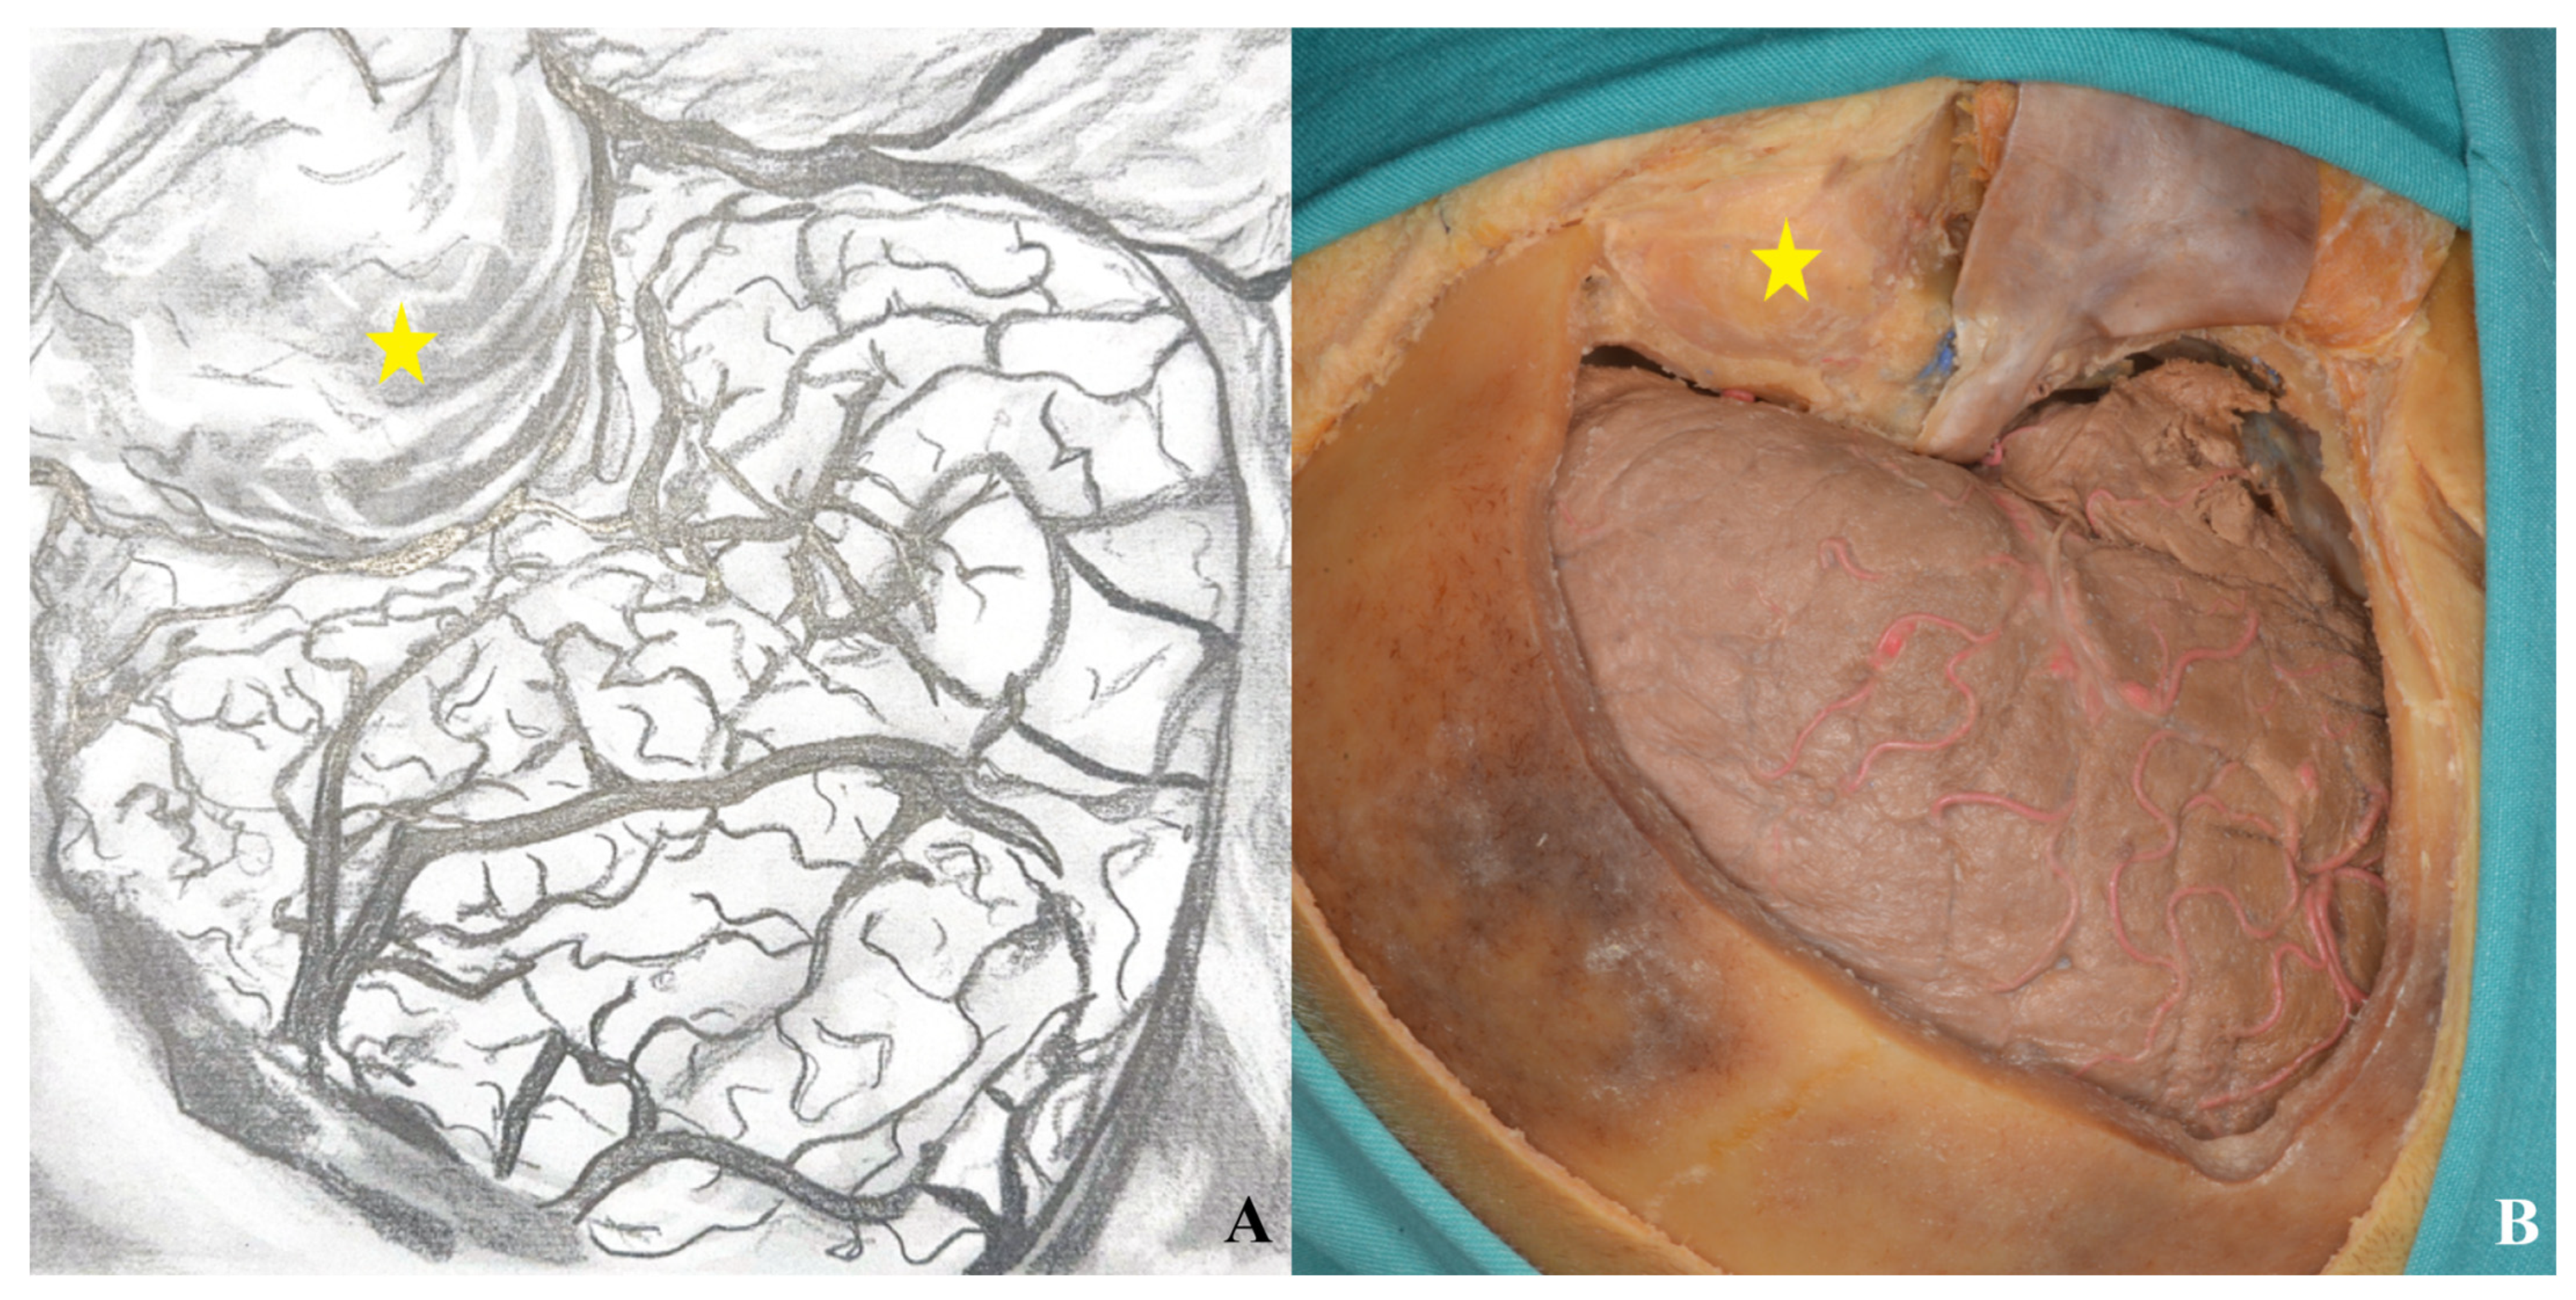

3.1. Pterional Craniotomy

3.1.3. Craniotomy

3.1.4. Basal Drilling

3.1.5. Dura Incision